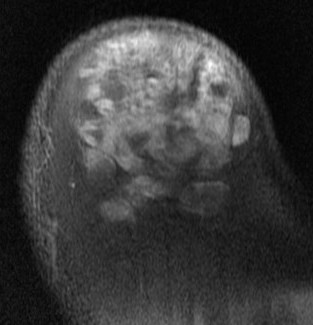

MRI

Deep to fascia / heterogenous